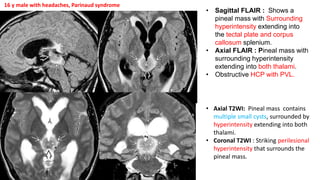

• Sagittal FLAIR : Shows a

pineal mass with Surrounding

hyperintensity extending into

the tectal plate and corpus

callosum splenium.

• Axial FLAIR : Pineal mass with

surrounding hyperintensity

extending into both thalami.

• Obstructive HCP with PVL.

• Axial T2WI: Pineal mass contains

multiple small cysts, surrounded by

hyperintensity extending into both

thalami.

• Coronal T2WI : Striking perilesional

hyperintensity that surrounds the

pineal mass.

16 y male with headaches, Parinaud syndrome